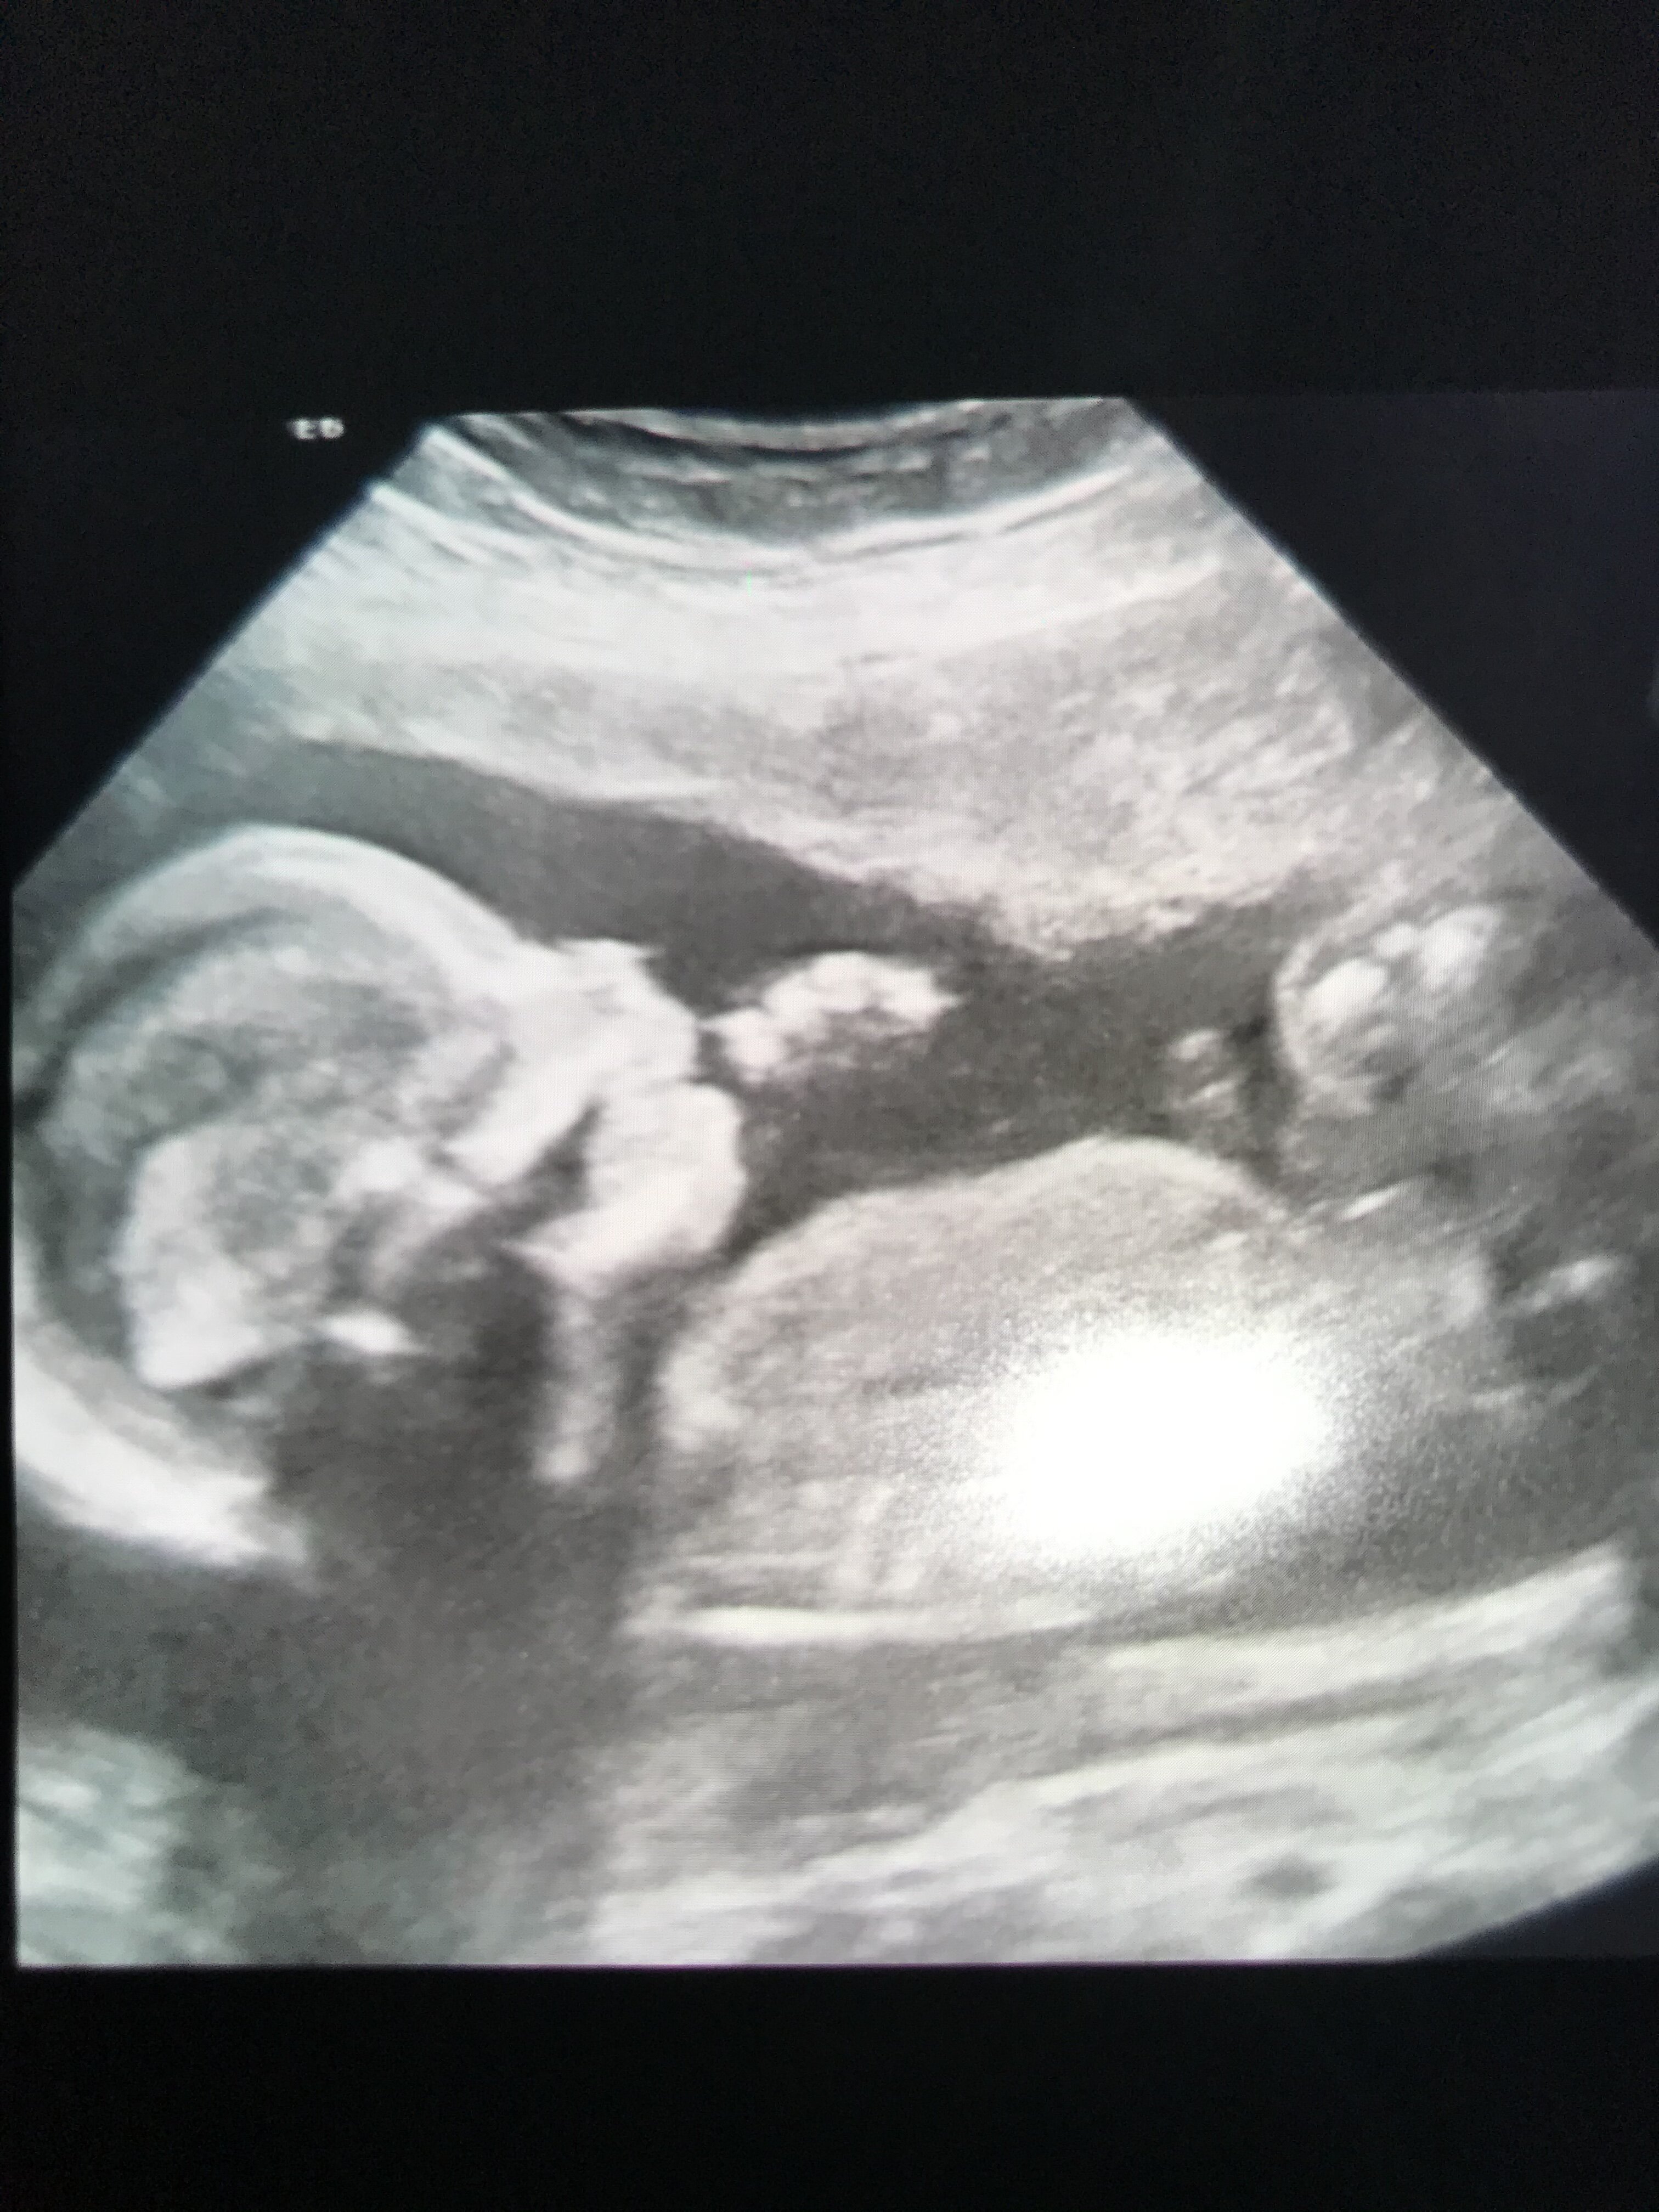

A tak naprawde to szybko zaszlam w kolejna ciaze i jedyne czego sobie zycze to porod bez komplikacji,bo pierwszej mlodosci nie jestem i zdrowy beybiśZobacz załącznik 1261971

U mnie było 321 g w równym 20 tygodniuJa już po USG połówkowymtrochę mnie lekarz zmartwił bo wielkość maleństwa nie pasuje do tygodnia. Jest różnica prawie 1.5 tyg. Mam skontrolować za 4 tygodnie jak rośnie.